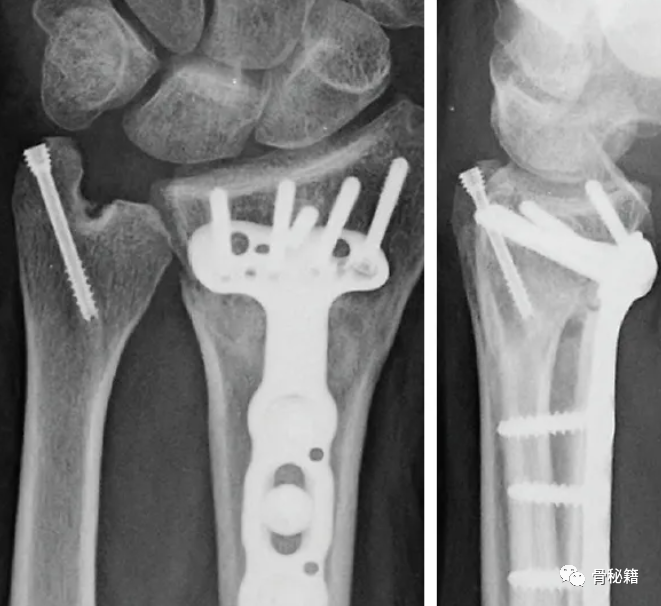

拧入空心螺钉

固定后 术中用探钩检查TFCC稳定性,发现固定后稳定性较好